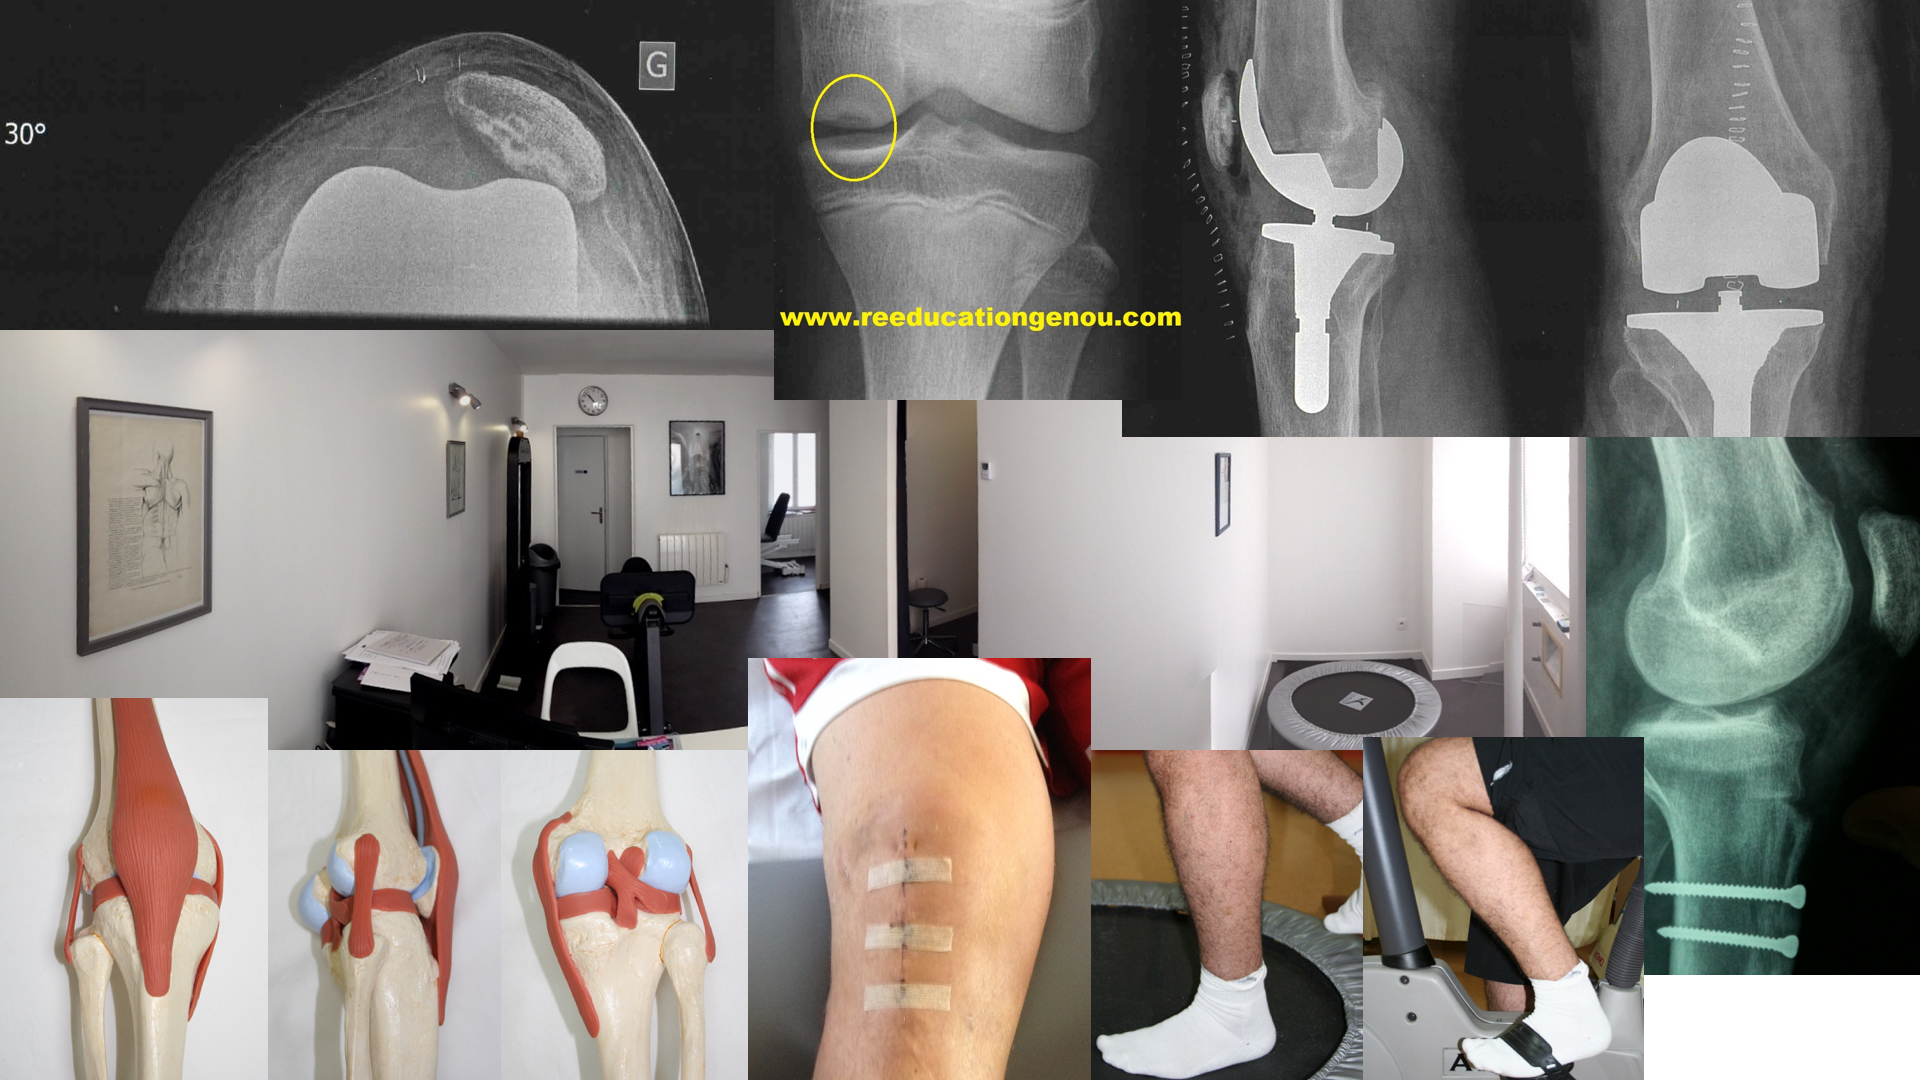

ce site destiné aux patients

Ce site se base sur plusieurs centaines de bibliographies chirurgicales et recommandations internationales des chirurgiens et médecins de rééducation concernant la rééducation du genou opéré ou non ainsi que la prise en charge expliquée et parfois imagée des lésions du genou rotulien ligamentaire prothétique et méniscal.